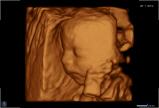

Seit März 2019 steht ein neues 3D/4D-Ultraschallgerät für faszinierende Eindrücke von Ihrem Baby zur Verfügung.

Außer den Fotos können auch 3D/4D Viedeoclips gemacht und auf einem USB-Stick gespeichert werden. So können die Bilder und Clips jederzeit angesehen werden.